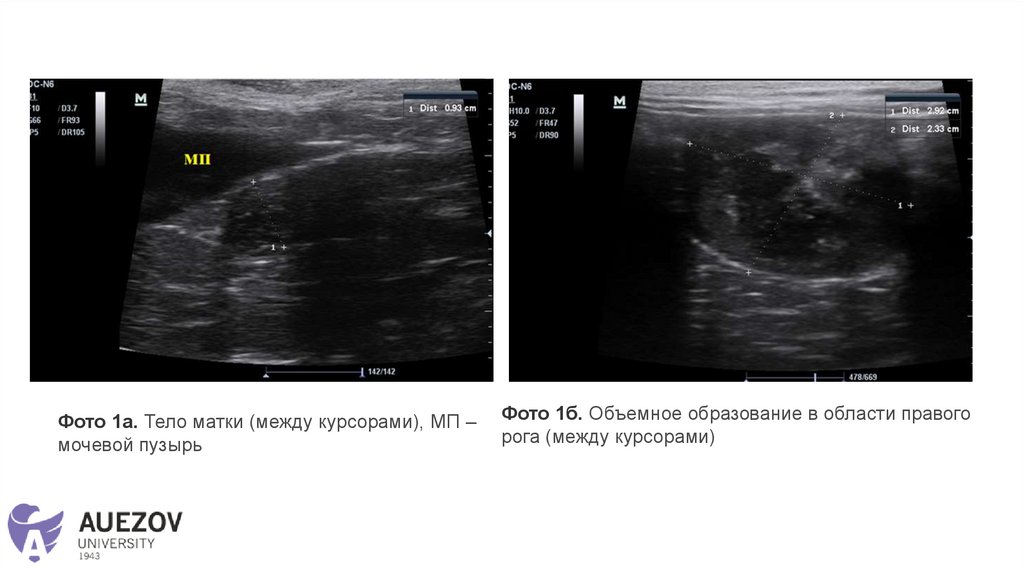

Ультразвуковое исследование

• Наличие свободной жидкости в брюшной полости: не визуализируется.

• Матка: визуализируется. Размер: диаметр тела матки 0,6 см.

Гипоэхогенной однородной структуры с гиперэхогенной линией по центру.

Просвет локально расширен гипоэхогенным жидкостным содержимым до 1

см.

Рога матки: визуализируются. Левый рог диаметром 0,45 см.

Гипоэхогенной однородной структуры. Просвет не расширен.

В области правого рога визуализируется объёмное образование размером

2,9*2,3 см, неоднородное, гиперэхогенное с анэхогенными полостями

(жидкостное содержимое с гипоэхогенной взвесью), границы четкие,

контуры ровные, васкуляризация умеренная.

• Наличие плодов: нет.

Заключение:

• На момент исследования УЗ-признаки - изменений тела

матки более характерных для

пиометры/гемометры/мукометры и объёмного образования

в области правого рога матки - более характерно для

абсцесса (нельзя исключить неопластический процесс)

Фото 1а. Тело матки (между курсорами), МП –

мочевой пузырь

Фото 1б. Объемное образование в области правого

рога (между курсорами)